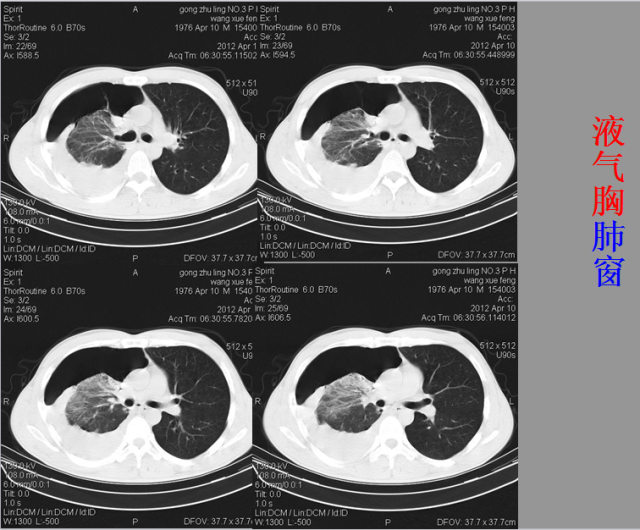

急胸症篇

04